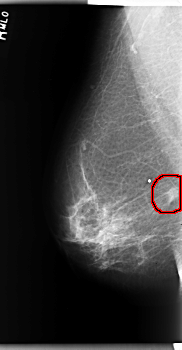

C_0202_1.RIGHT_MLO

RIGHT_MLO LINES 5936 PIXELS_PER_LINE 3080 BITS_PER_PIXEL 12 RESOLUTION 50 OVERLAY

FILE: C_0202_1.RIGHT_MLO.OVERLAY

TOTAL_ABNORMALITIES 1

ABNORMALITY 1

LESION_TYPE MASS SHAPE IRREGULAR MARGINS SPICULATED

ASSESSMENT 5

SUBTLETY 5

PATHOLOGY MALIGNANT

TOTAL_OUTLINES 1

BOUNDARY